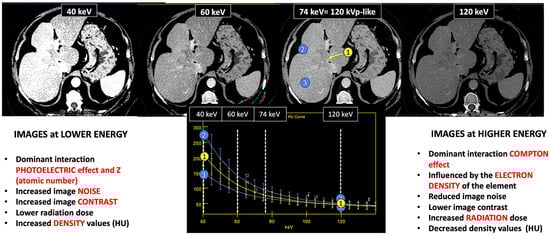

Figure 2.

DECT images corresponding to a patient with cholangiocarcinoma evaluated at 40, 60, and 74 keV. Energy level deeply influences many image features (contrast, density values, image noise, etc.). Materials with a high atomic number, such as iodine, are susceptible to the photoelectric effect at lower energy levels. Note the differences in the spectral curves of cholangiocarcinoma (region of interest [ROI] corresponding to yellow circle 1), peritumoral area with increased enhancement (ROI blue circle 2), and normal liver parenchyma (ROI blue circle 3) due to their different iodine uptake. Furthermore, it is shown that at high energy levels (e.g., 120 keV) it is not possible to distinguish between them. Density values also change. Cholangiocarcinoma attenuation values at 120, 74, and 40 keV are 52 HU, 80 HU, and 213 HU, respectively, with increased values at lower energy.